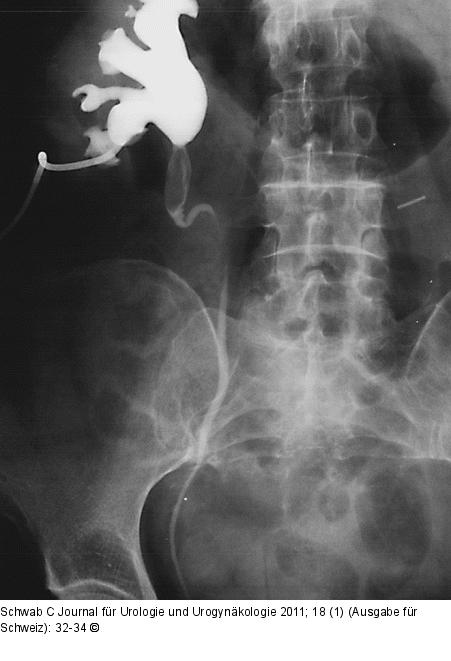

Abbildung 3: Nephrostomie

Einlage einer perkutanen Nephrostomie bei obstruktiver Pyelonephritis |